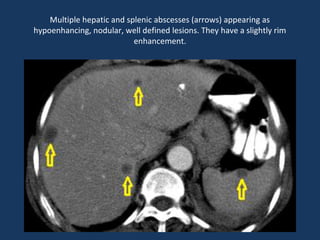

Lesions are hypoattenuating at CT with irregular ill-defined margins and

minimal central but definite peripheral contrast enhancement

Multiple hepatic and splenic abscesses (arrows) appearing as

hypoenhancing, nodular, well defined lesions. They have a slightly rim

enhancement.

Lesions are hypoattenuatingat CT with irregular ill-defined margins and minimal central but definite peripheral contrast enhancement

Multiple hepatic andsplenic abscesses (arrows) appearing as hypoenhancing, nodular, well defined lesions. They have a slightly rim enhancement.